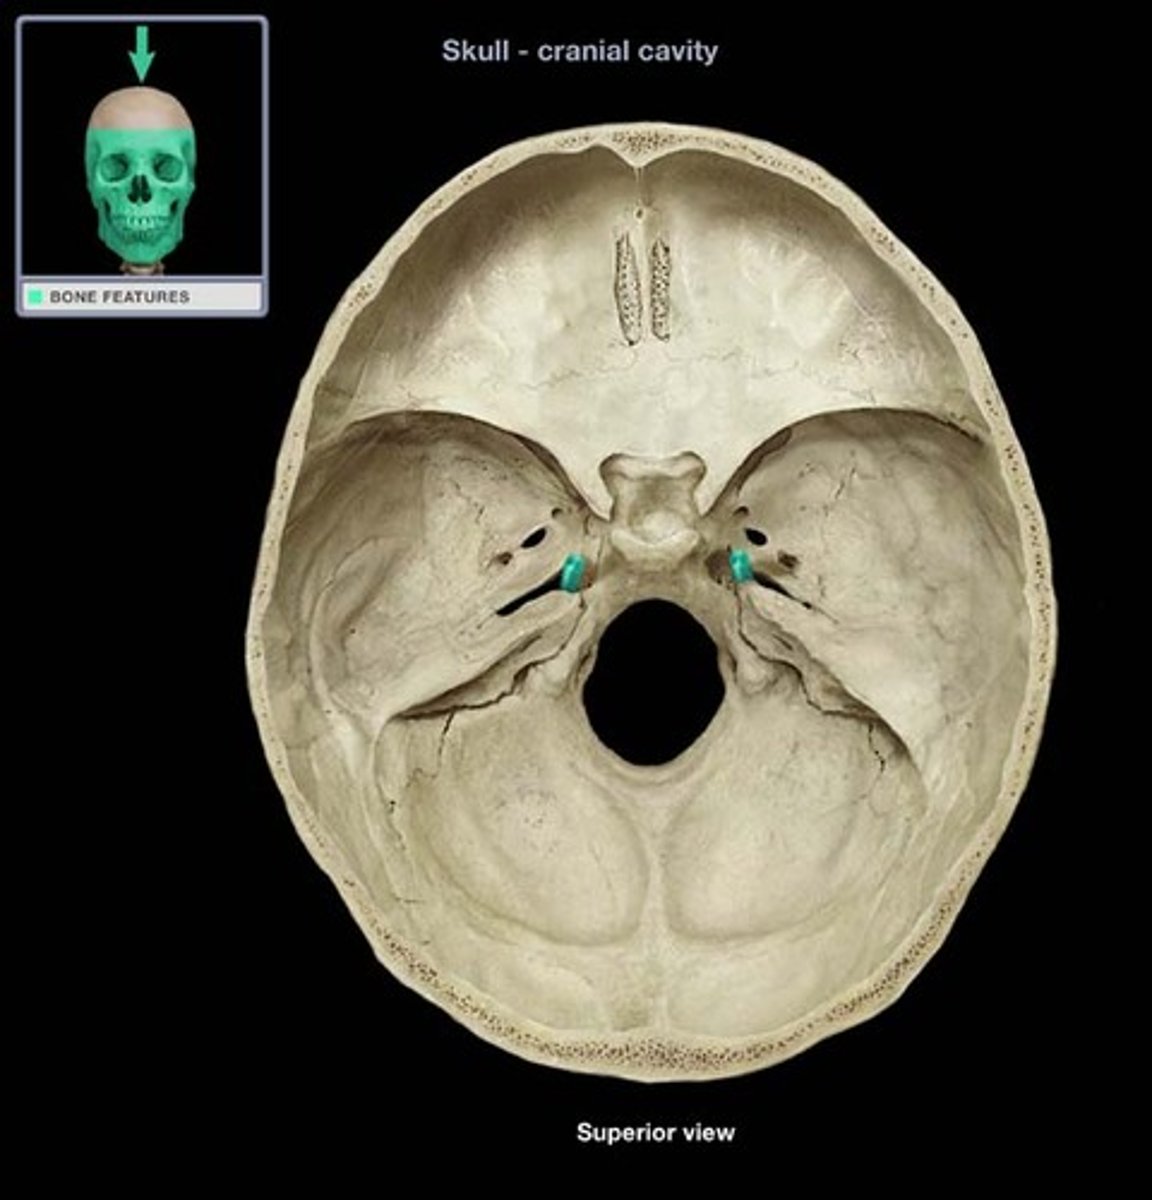

Carotid Canal

Jugular foramen